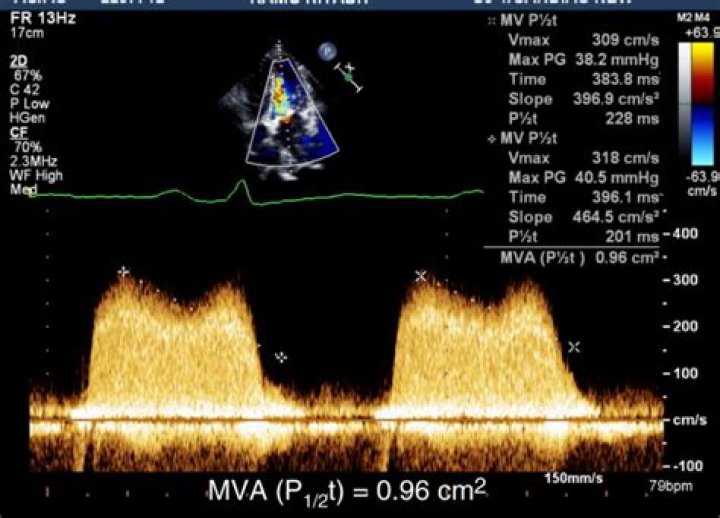

The PHT of the mitral inflow deceleration slope was determined from the stored mitral inflow Doppler VTI, and the MVA was then calculated using the following formula: MVA = 220/PHT (Figure 1) [10].

The time from the Vmax to the velocity equal to Vmax divided by 1.4 is the pressure half time. (Vmax / 1.4 is equivalent to the half pressure). 220 divided by the PHT is the mitral valve area.

Calculation of the pressure half-time (PHT) is achieved by measuring the time from peak E wave velocity (V1) to the point when velocity equals peak velocity × 0.71 (V2) (calculations in white) and by measuring the deceleration time from the extrapolated E–F slope and multiplying by 0.29 (calculations in yellow) (D).

Doppler echocardiography is useful in assessing the severity of obstructive cardiac lesions, such as mitral valve stenosis. The Doppler study can be used to calculate pressure half-time (PHT), which is defined as the time required for the pressure gradient across an obstruction to decrease to half of its maximal value.